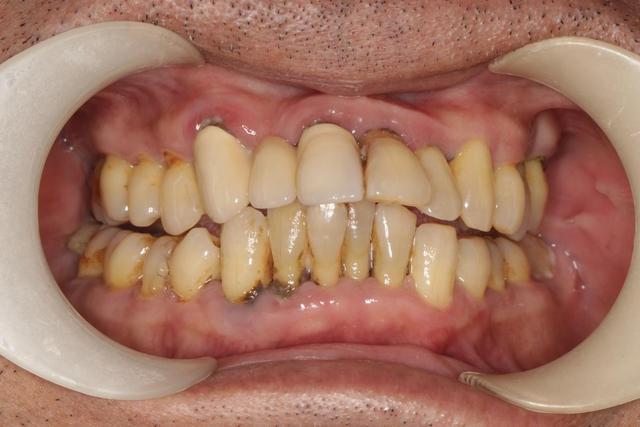

牙齿问题从来不仅仅是口腔的事。牙齿作为全身健康的重要窗口,可以反映身体多种潜在问题。牙痛,可能不仅仅因为蛀牙或口腔感染,很多全身性疾病的初期信号就藏在牙疼的背后。

牙齿连接着牙龈血管和身体其他器官,感染可能迅速扩散,轻则引发局部问题,重则导致全身并发症,甚至危及生命。

尤其是牙龈脓肿、牙髓感染等情况,容易因处理不及时而引发败血症、心内膜炎或呼吸系统感染。这些看似遥远的疾病,往往埋藏在牙病之后,稍有大意,后果难以想象。

牙龈出血、牙周袋形成或牙龈肿痛,可能是炎症的早期标志,如果不介入治疗,细菌会缓慢侵入深部组织,增加全身感染风险。